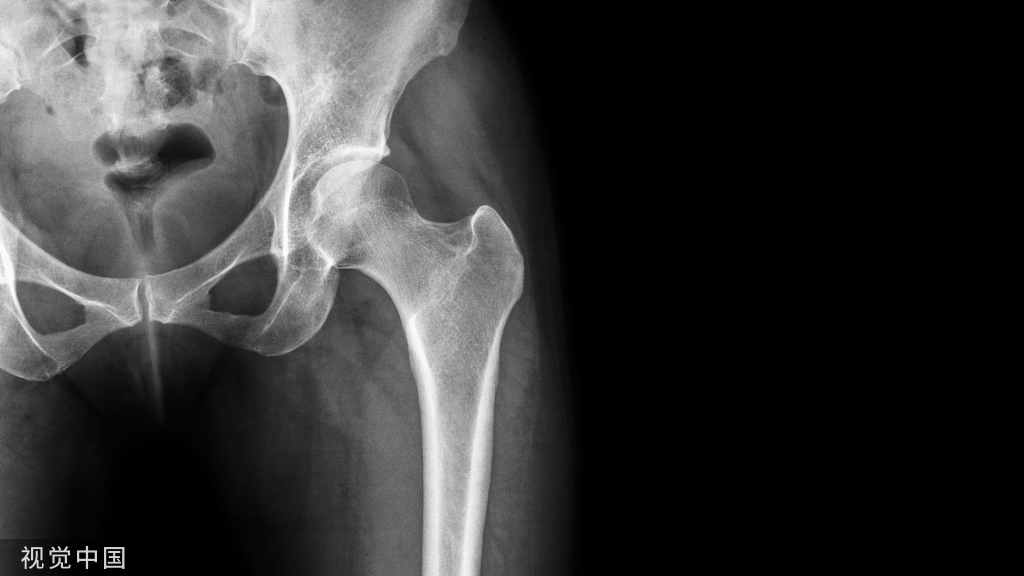

A1.3型骨折常出现的前后成角可以通过顶棒来复位

外侧壁移位也可以通过钉棒技术来进行复位